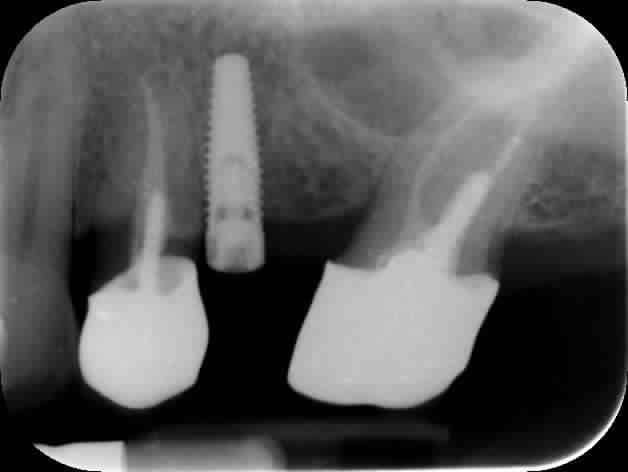

Pour la première fois, j'ai placé un implant très proche d'une dent adjacente. Et j'avoue que je ne m'en suis apperçu qu'une fois la radio prise.

J'aimerais savoir ce qui m'attend. Y a t il un risque pour l'ostéo-intégration? Plus grave, pour 24? Quels sont les difficultés qui m'attendent au moment de la prothèse?

A mon avis, vu la radio, la 24 a l' air bonne pour l'extraction, non pas à cause de ton implant mais de l'ajustage de la couronne.

C'est mes yeux ou la 24 présente une énorme carie sous la couronne? Si c'est le cas tu pourras rectifier le tir lorsque tu poseras l'implant pour cette dent

Contre toute attente, l'image que vous voyez sous la couronne est un artéfact et il n'y a pas de carie au niveau de 24.

J'étais tellement focalisé sur le sinus que je ne voulais pas toucher que je suis parti trop proche de 24.

Tu es dans l'axe de l'edentement et le cas était pourri depuis le départ: 26 très versé, édentement étroit de point de contact à point de contact: grosse rétention alimentaire à prévoir en 25 26

Maintenant tu dis 'je vais devoir faire du transvissé'. Pourquoi plus qu'un pilier ? Une transvissé est possible quand l'implant est placé idéalement car c'est plus difficile de rattraper un axe qu'avec un pilier.

J'aimerais voir une radiographie avec un angle plus antéro-postérieurs?